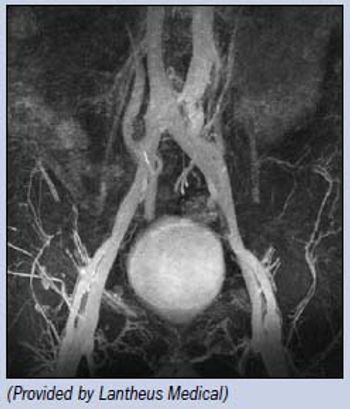

Ablavar, the only commercially available blood pool MR contrast agent, lights up vasculature in this steady-state MR angiogram.